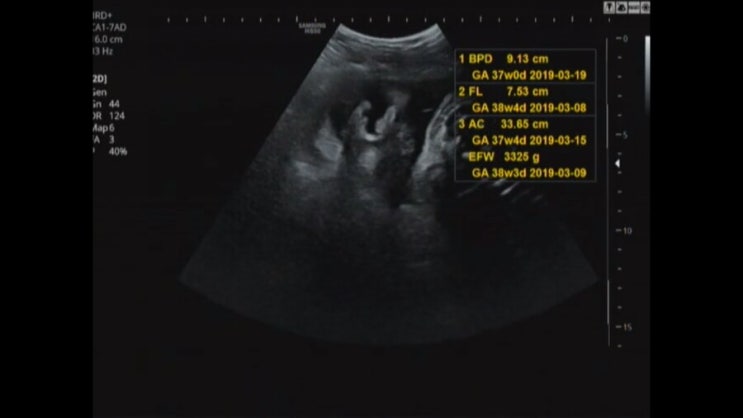

[임신기록]38주6일,폭풍태동,양수인가아닌가,정기검진

지난주.. 마지막 인줄알았던 정기점진ㅎㅎ 진통오면 병원가려고 했는데 새벽에 화장실갔다왔는데 뭔가 내스...